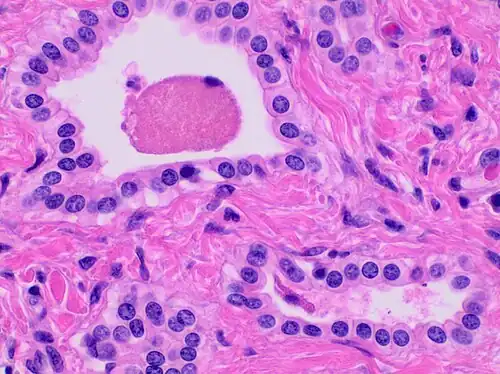

Histopathology of a bile duct hamartoma, high magnification, H&E stain. It shows typical features of bile duct hamartoma: Small to medium sized, irregularly shaped bile ducts lined by bland cuboidal epithelium (may also be flattened). Prominent intervening collagenous stroma. Bile ducts containing eosinophilic debris (may also contain inspissated bile) -